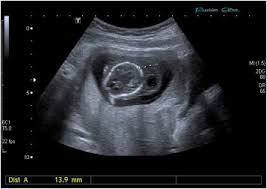

ماهو كيس الحمل ؟ ومتى يظهر الجنين في كيس الحمل ؟

كيس الحمل هو عبارة عن نسيج أو تركيبة الأنسجة التي تحيط النطفة آلام في أوائل أيام فترة الحمل ويكون كروب الشكل أو دائري وهو ينمو بمعدل ١ ملي في اليوم الواحد منذ نهاية الأسبوع الرابع حيث أنه يمكن أن يظهر بعد أن يمر ٣ أسابيع تقريبا علي الحمل ويكون سمك كيس الحمل حوالي من ٢ إلى ٣ ملي ويبدأ ظهور هذا الكيس داخل الرحم بعد مرور ما يعادل ٥ أسابيع تقريبا بعد فترة الحمل ويجدر الإشارة ان التصوير بالموجات فوق الصوتية من خلال المهبل يكون ادق وافضل من التصوير عبر الموجات فوق الصوتية عبر البطن ولكنه لا يفضل في بداية الحمل ويظهر كيس الحمل عند التصوير بالمجان الصوتية عبر البطن عندما تكون نسبة هرمون الحمل عالية وتصل إلى ١٥٠٠ الي ٢٠٠٠ وحدة ولذلك يظهر الحمل بعد إجراء اختبار الحمل وفي فترة مبكرة أي بعد حوالي مرور ٧ أيام فقط من عملية التبويض أو الإخصاب.

متى يظهر الجنين في كيس الحمل ومتى يكون كيس الحمل فارغا ؟